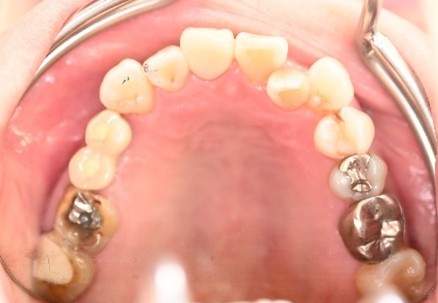

男性Kさん 50代(インプラント)

歯がグラグラするところ、むし歯のところ、しみるところ、被せ物がとれたところ、歯茎が腫れて血が出るところ、歯が抜けているところがある。すべて治したい。

治療内容

残っている歯を抜歯し、上下インプラント治療をしました。

所感

歯周病が進行している歯、むし歯が進行している歯がほとんどで、レントゲンを撮り、詳しく診てみると、ほとんどの歯を保存することができないことがわかりました。抜歯後は、入れ歯かインプラントの方法があります。治療開始前に患者さんに詳しく現状を説明し、治療法についてじっくり相談しました。自分の歯と同じような感覚で食事できるインプラント治療を選択されました。治療後、表情がとても明るくなり、口元がとても自然で10歳以上若返ったように感じました。「時間はかかりましたが、インプラントにして本当に良かったです!」と素晴らしい笑顔でお話ししてくださいました。

上顎:¥3,280,000(税込)

下顎:¥3,280,000(税込)